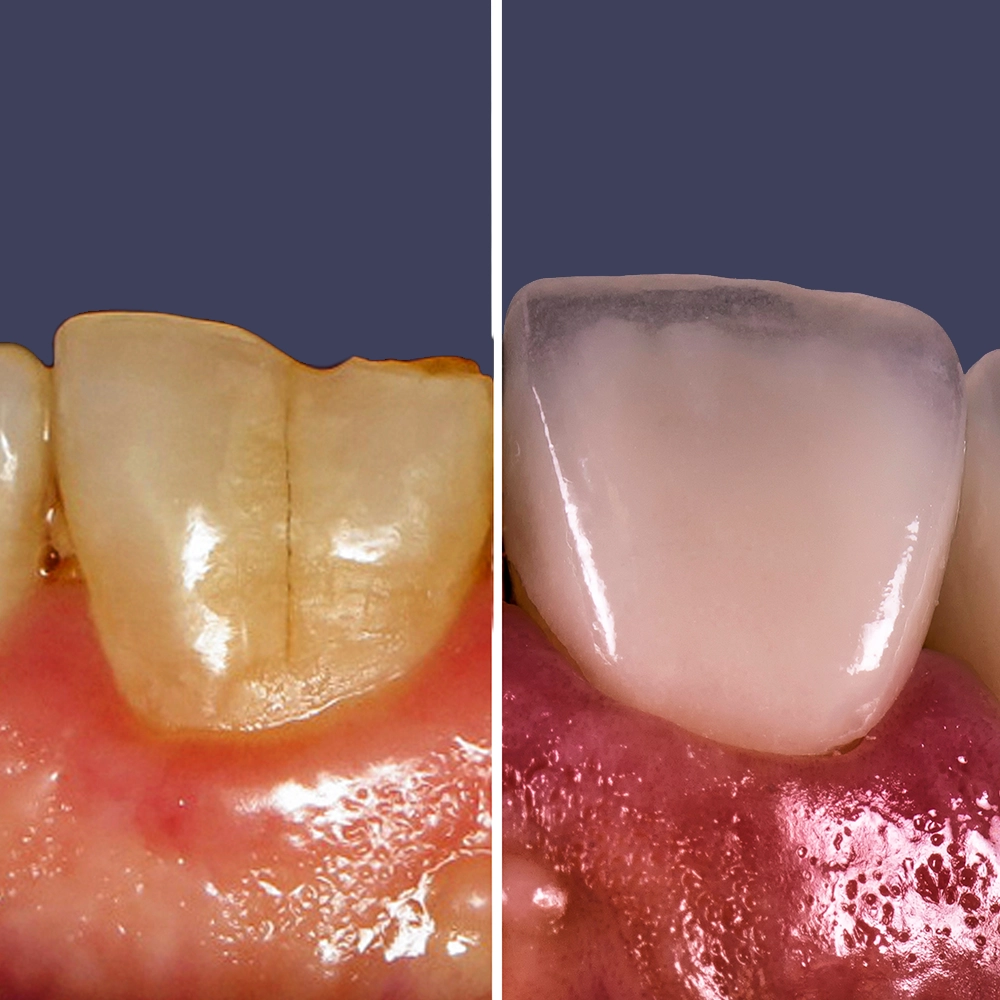

One of the most significant benefits of ultra-thin veneers is that they require minimal removal of the tooth surface, allowing you to preserve your natural tooth structure. Traditional veneers often necessitate the removal of a substantial amount of enamel, which can weaken the teeth over time. In contrast, ultra-thin veneers are designed to be as thin as a contact lens, which means that only a small amount of your tooth surface needs to be etched. This preservation of your natural enamel results in a healthier, stronger tooth that maintains its integrity and function.

Ultra-thin veneers are crafted from high-quality materials that closely resemble the look and feel of natural teeth. The translucency and texture of these veneers mimic the appearance of real enamel, ensuring that your smile looks natural and aesthetically pleasing. Each veneer is custom-made to match the color, shape, and size of your existing teeth, blending seamlessly with your natural smile. This attention to detail ensures that your veneers are virtually indistinguishable from your natural teeth, providing you with a flawless, beautiful smile.

Ultra-thin veneers offer a less invasive alternative to traditional veneers and the procedure is completely different (see above). Traditional veneers often require significant removal of tooth enamel, which can weaken the teeth. In contrast, ultra-thin veneers require minimal tooth alteration, preserving more of your natural tooth structure. This results in a stronger, healthier tooth foundation and a natural-looking appearance. Additionally, ultra-thin veneers are often quicker to apply and cause less discomfort during the procedure.